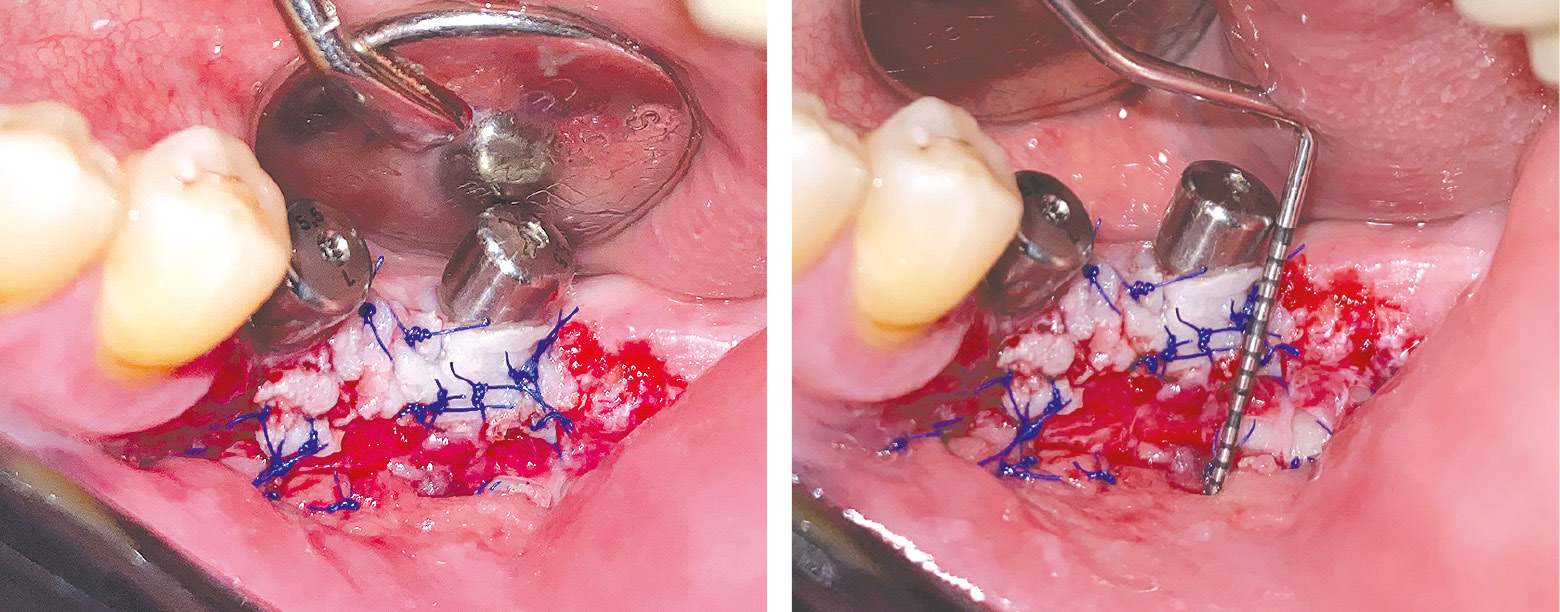

FGG was harvested from the palatal mucosa in the region of teeth 13–17 (ISO/FDI designation). A No. 15C blade was used to make the first horizontal incision 3 mm apical to the gingival sulcus, angling the blade at 45° to a depth of 1.0–1.5 mm. Mesial and distal incisions were then made to define the graft borders, followed by split-thickness flap elevation. While gently holding the flap with tissue forceps, a parallel incision to the initial one was performed to determine the graft width. Glandular inclusions and residual adipose tissue were removed with a scalpel (see Fig. 3). The graft was then positioned onto the recipient bed and sutured to the periosteum using ArmaPVDF 5-0 sutures with a 3/8-circle cutting needle (see Fig. 4).

Fig. 4. Postoperative appearance of the surgical site.

Under infiltration anesthesia with 0.7 mL of 0.00001% articaine solution, a FGG was harvested from the palatal mucosa using the same 980 nm diode laser in pulsed ablation mode at 1.2 W. The inner surface of the graft was treated by laser vaporization to remove adipose and glandular tissue inclusions, ensuring a uniform graft thickness. Next, with the fiber tip held 0.5–1.0 cm away from the donor site, a defocused laser beam was applied to create a coagulated surface layer, known as a “laser dressing,” which promotes hemostasis and sterile wound coverage on the palatal donor area. The prepared graft was positioned in the recipient bed and sutured to the periosteum using ArmaPVDF 5-0 suture material with a 3/8-circle cutting needle.